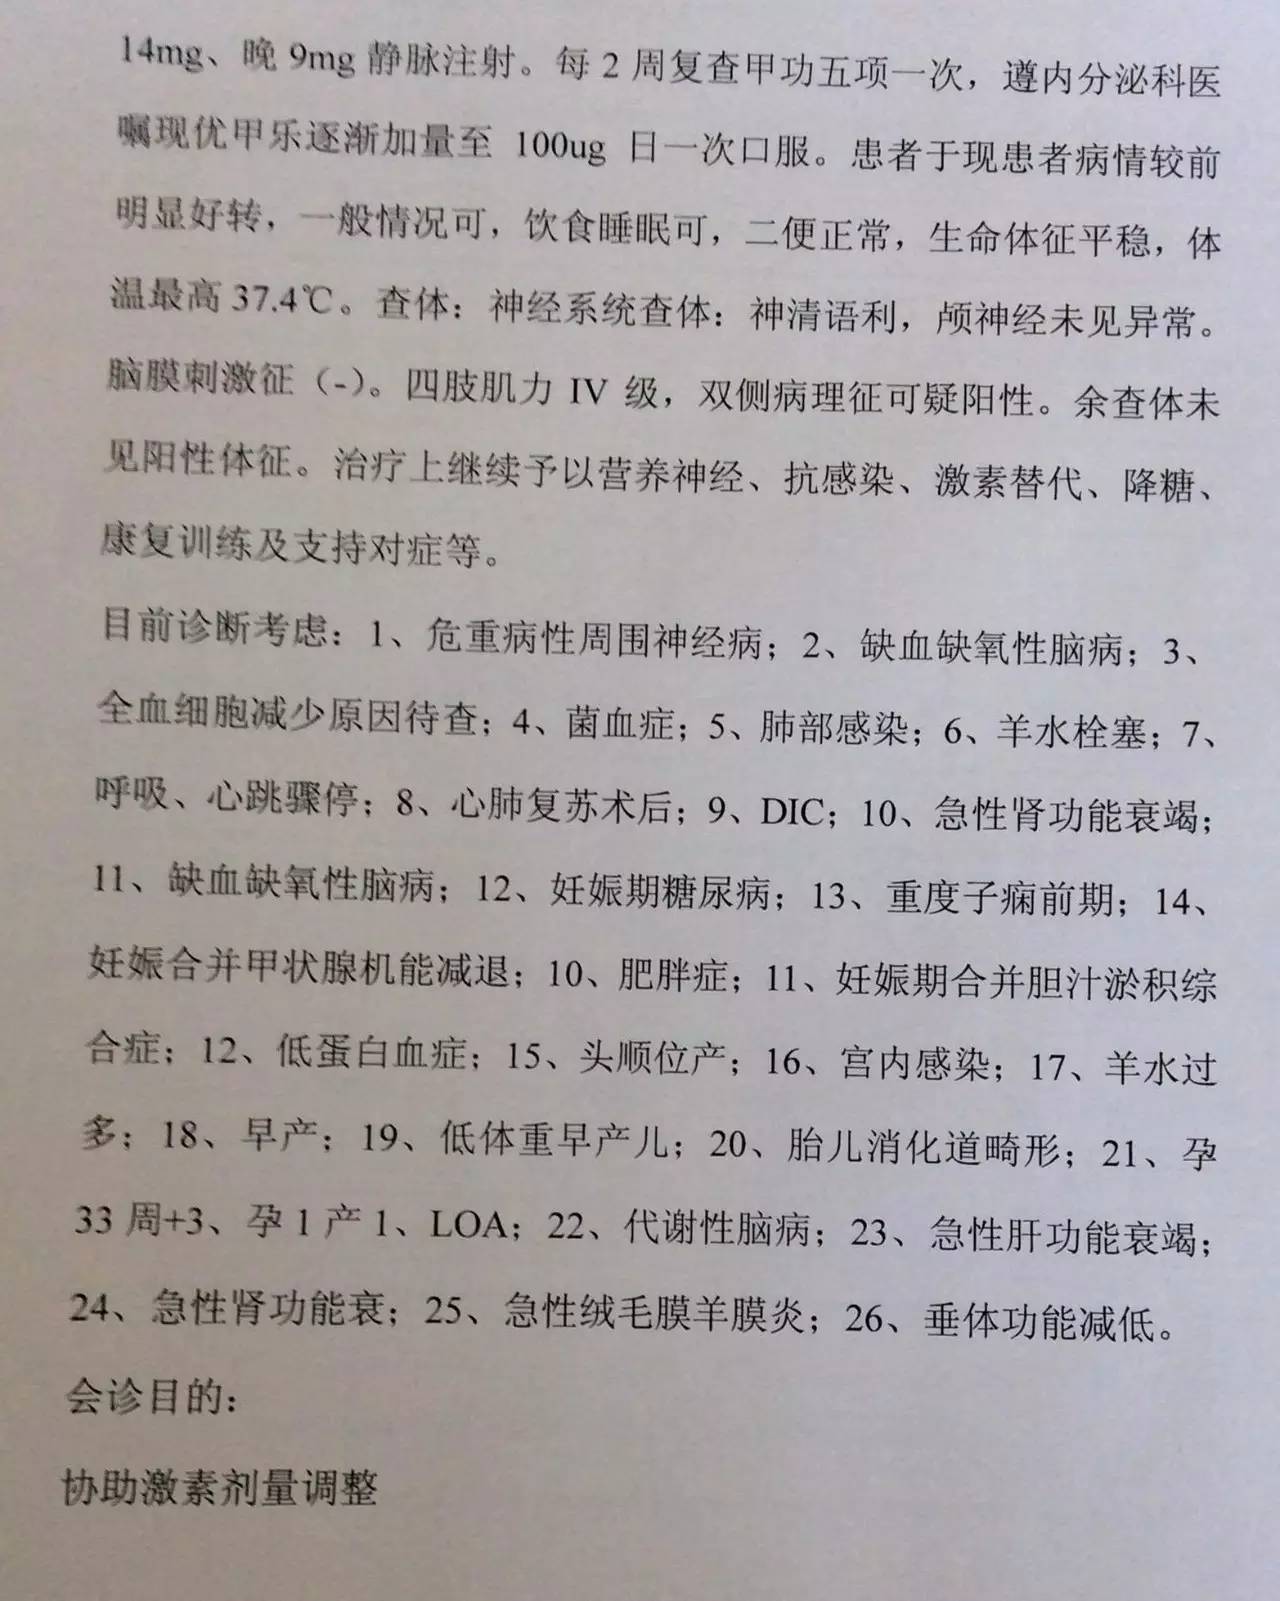

目前患者面临的问题是出现了甲状腺功能减退症和肾上腺激素需要减量的问题。结合患者产后一系列的意外和抢救过程,要警惕患者出现Sheehan syndrome(希恩综合征),因为低血压、出血等等引起垂体缺血缺氧所致。

1.甲状腺功能减退症:因为患者属于继发性甲状腺功能减退症,因此根据FT4水平来调整优甲乐的剂量即可,目前加量到100μg/天,同意这种调整;

2.患者应用甲强龙,当时是因为出现了休克为了抢救所用,目前情况明细好转,可以每周(也就是贵院内分泌大夫会诊的7~10天)减量甲强龙1片(4mg); 但因为患者可能存在继发性肾上腺皮质功能减退症(继发于希恩综合征),减量到全天2片时需要评估清晨未服药前ACTH和血皮质醇、电解质、性腺激素六项来评估是否能够完全停药,还是需要减成替代剂量,此时可以应用泼尼松来替代甲强龙,泼尼松一片是5mg,等效于甲强龙1片,4mg,如果确实出现肾上腺皮质功能减退,可以逐渐减量到泼尼松全天1片(2.5mg,早上和下午各服用一片)。到时候再根据患者复查的情况判断肾上腺功能的恢复情况。